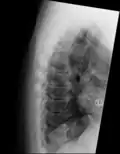

![]() | |

| DISH in an 80 year old female, also with T11 fracture. | |